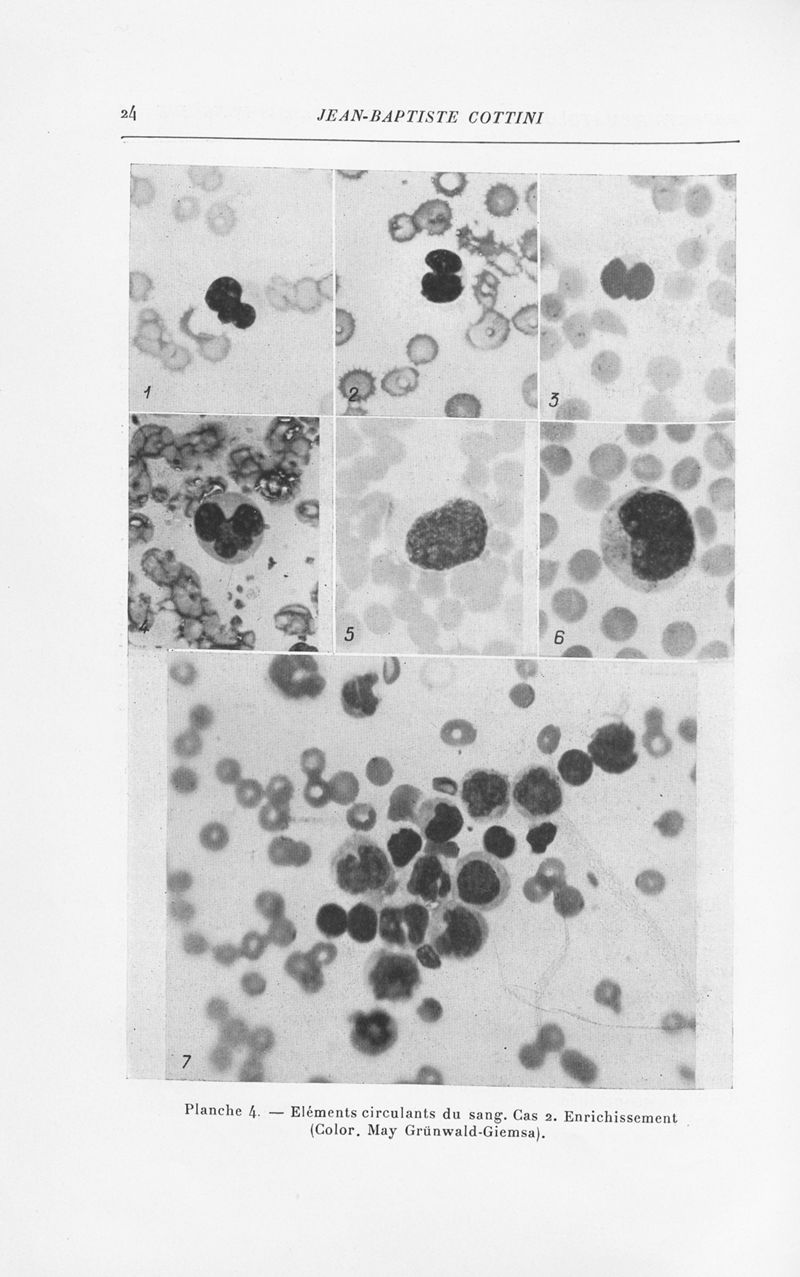

Annales de dermatologie et de syphiligraphie

7ème série, tome VIII. - Paris : Masson, 1937.